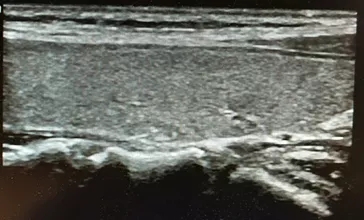

图1 甲状腺良性结节消融前横切位 42×20×18mm

女性,30岁,发现右侧颈部包块1年余入院。

查体:右侧甲状腺可触及大小4cm左右包块,质地韧,可以随着吞咽上下活动,无明显压痛。

彩超:右侧甲状腺内可见大小42×20×18mm实性包块。

术前细胞学穿刺:结节性甲状腺肿。